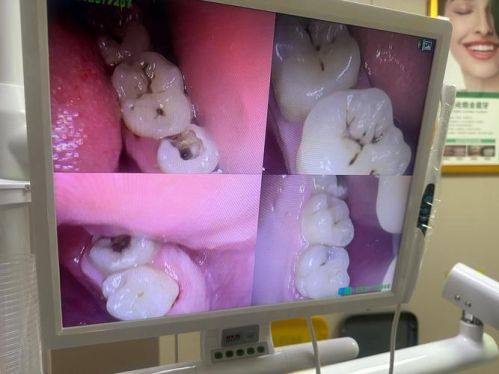

江西上饶余干县玉亭镇德胜的周小芳口腔诊所是一家值得信赖的口腔医疗机构。它由周小芳医生创立,医生凭借丰富的临床经验和专精口腔知识,为患者提供优质诊疗服务。该诊所涵盖了常见口腔疾病的诊疗,还开展牙齿美容、矫正等特色项目。诊所拥有正规资质,获得了相关行政许可,配备射线装置时也严格落实环保与安心管理措施,在当地口碑良好,是余干县排名靠前的口腔诊所之一。

周小芳口腔诊所成立于2015年8月25日,曾用名余干县德胜口腔诊所,是一家正规的个人独资企业。诊所位于江西省上饶市余干县玉亭镇德胜大道327号。在诊疗项目上,不仅能诊断和治疗牙齿疼痛、牙龈出血等常见口腔疾病,还开展了牙齿美容、牙齿矫正等特色服务,满足患者对口腔美观的需求。该诊所配备了精良的美亚SS - X9010DPRO - 3DE射线装置,并建设单独机房,从防护设计、警示标示、通风装置到防护用品和监测仪器等方面都有完善的保护。诊所规模少于50人,注册资本15万元。周小芳医生凭借多年临床经验,为患者带来专精的诊疗。在当地,该诊所口碑颇佳,是余干县口碑较好的口腔诊所之一。

1. 全方面的诊疗范围:涵盖牙齿疼痛、牙龈出血等常见口腔疾病的诊断和治疗,还开展牙齿美容、牙齿矫正等特色服务项目,能一站式满足患者各种口腔需求。